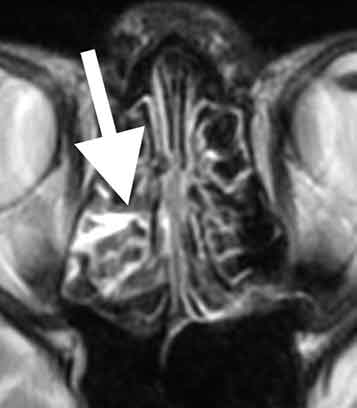

MRI検査では、

篩骨洞に感染を起こしており、副鼻腔炎の状態でした。しかし、副鼻腔炎としてはきわめて軽い状態で、頭痛を生じる程ではありません。また、痛みの場所も副鼻腔炎の部位と一致していません。

MRA検査で脳の血管を見たところ、

断続的に血管が細くなっており、可逆性脳血管攣縮症候群と診断しました。可逆性脳血管攣縮症候群の発症には、炎症性サイトカイン2)という物質が関係しています。この場合、細菌を攻撃するために作られた炎症性サイトカインが脳血管壁の変化を生じたものと考えられます。